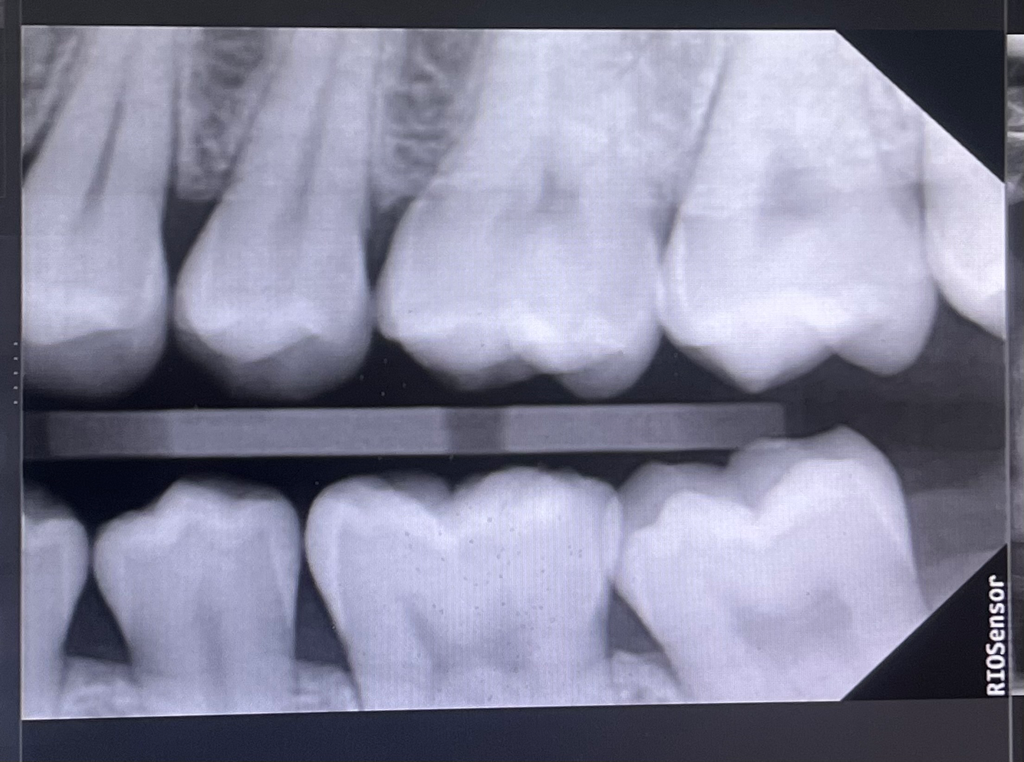

엑스레이 상으로는 큰 인접면 충치는 보이지 않습니다. 일단 자켜보시는게 좋을것같습니다

인레이가 필요한 것으로 보이지는 않습니다만 사진의 해상도에 따른 진단의 차이가 있으니 한곳만 더 가보시는게 좋겠습니다.